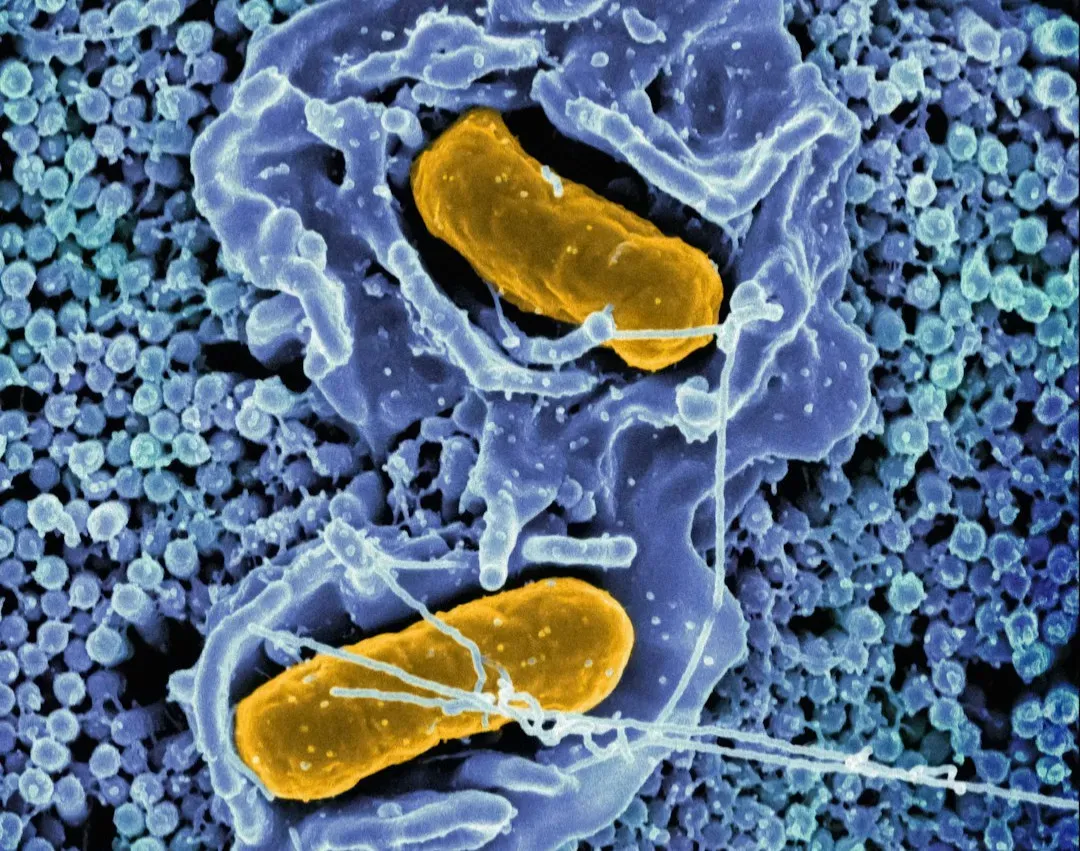

The Immune System’s “Memory” And Autoimmunity Paradox

Your immune system remembers past infections for years, sometimes for life, launching faster defenses if the same invader shows up again. That memory is the basis of vaccines and one of the great triumphs of biology. But the same system that can recognize a virus years later can also, for reasons we don’t fully understand, turn on your own tissues instead and cause autoimmune diseases like type 1 diabetes or multiple sclerosis.

Scientists have uncovered a lot about immune cells, antibodies, and inflammatory pathways, yet the line between healthy defense and self-destruction remains blurry. Why does one person’s immune system tolerate their own cells, while another’s mislabels them as enemies? Environmental triggers, gut microbes, infections, genetics – they’re all suspects, but there’s no single master explanation. It’s as if the body’s security guards not only learn faces but can occasionally become paranoid, and we still don’t know exactly what pushes them over that edge.